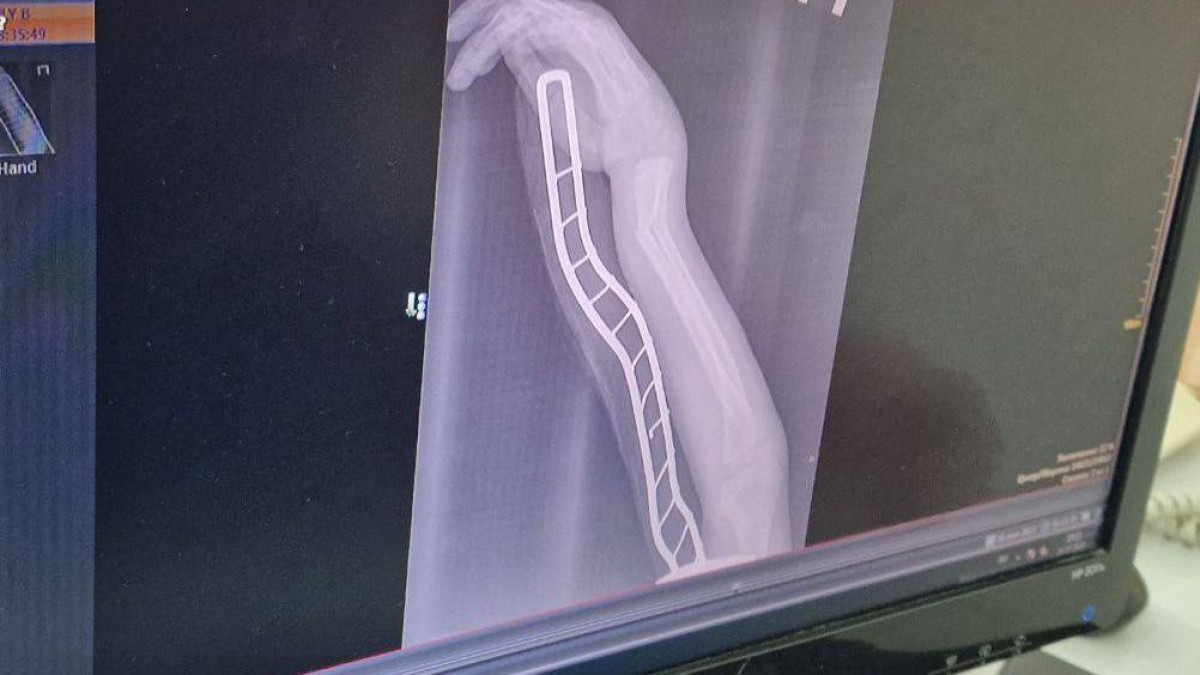

Восьмилетний Бауржан качался во дворе на качелях-балансире. Неудачное падение – закрытый перелом запястья со смещением. Травматолог Олжас Жунусов изучает рентгеновские снимки. Если кость при вправлении встанет на место, мальчику придётся месяц ходить в гипсе. Если нет, его ждёт операция, где кость придётся фиксировать металлическими штифтами. Пациент мужественно перенёс боль, руку фиксируют гипсом. Повторный снимок, и врач объясняет маме: как только спадёт отёк, нужен ещё один снимок, а ребёнку придётся походить несколько недель в гипсе.